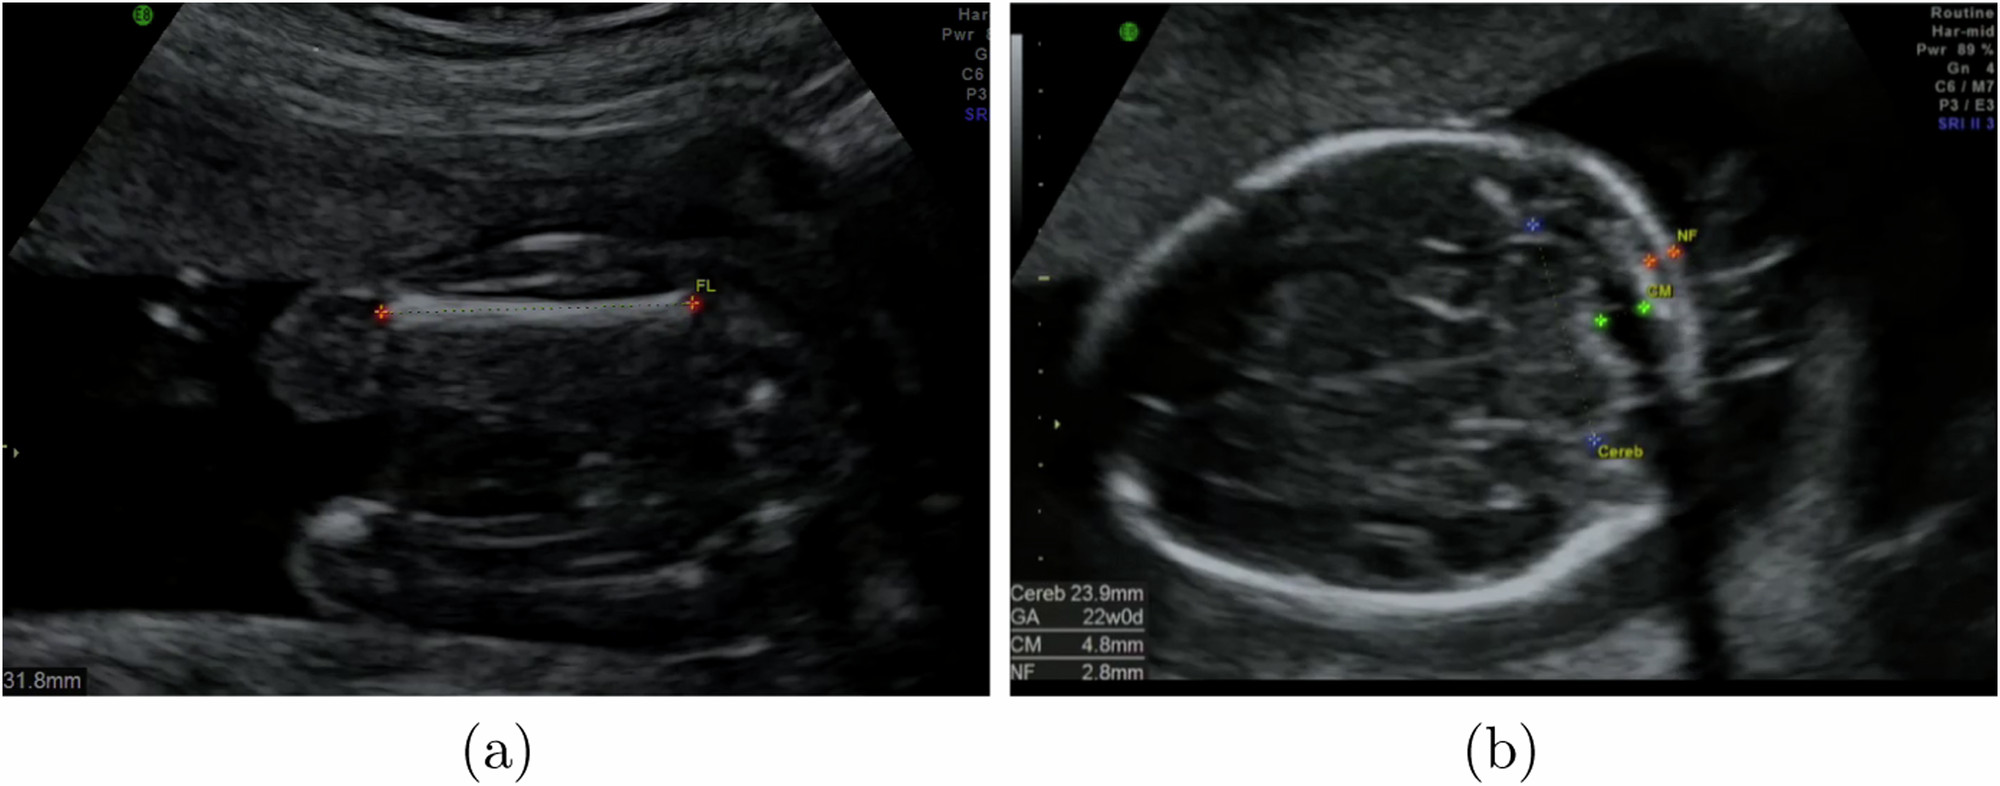

Fig. 7: Example heatmap outputs of our CaliperNet annotation extraction CNN.

Shown are extracted annotations for a a femur image, and b a brain-CB image with labels for the cerebellum, cisterna magna and nuchal fold. The cisterna magna and nuchal fold annotations were not used in this paper.